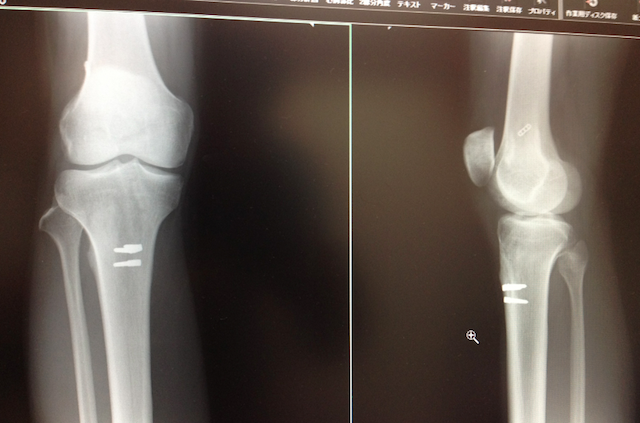

前十字靭帯再建手術後3ヶ月半のレントゲン、ボルトのようなものが再建した靭帯を抑えているのが見れます。手術後、海外出張が続いていてあまりリハビリができてませんでしたが順調な回復で一安心。徐徐にスポーツ、ジョギングや水泳などをして細くなってしまった右足の筋肉を戻そうと思います!